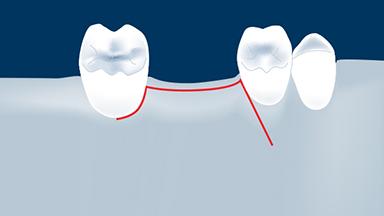

Flap Design

- describe the general principles for flap designs

- describe principles of flap design for implant surgery

- indicate flap designs for specific situations in implant surgery